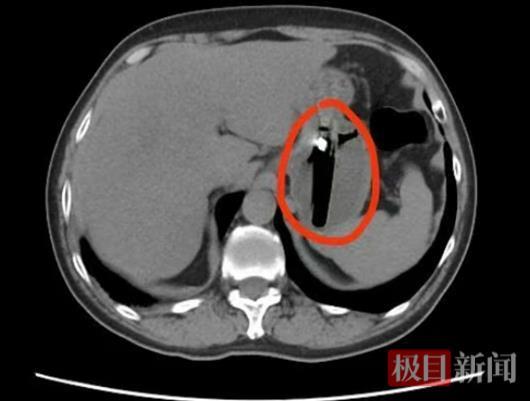

1月18日,陈先生突发上腹部绞痛,疼痛呈阵发性加剧,坐卧难安、恶心不止,紧急前往长江航运总医院·武汉脑科医院就诊。急诊胸腹部CT显示,陈先生胃内有一长约8厘米的异物。普外科二病区接诊医师郭敦伟通过追问其饮酒史和近期不适,初步推断为醉酒后误吞了打火机。郭敦伟解释,醉酒会导致咽喉部神经反射迟钝、判断力下降,且食管平滑肌松弛,使得本应被识别的异物顺利进入胃内。由于异物尺寸过长,无法通过幽门进入肠道自行排出,长期在胃内随蠕动反复摩擦胃壁,极易引发黏膜损伤甚至溃疡。更危险的是,胃酸持续腐蚀可能导致打火机外壳破损,内部易燃气体泄漏引发中毒,甚至穿透胃壁造成穿孔、腹膜炎。基于检查结果和病情评估,郭敦伟建议立即手术取出异物。